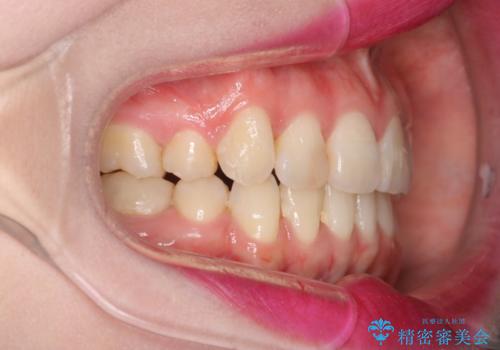

八重歯のワイヤーによる抜歯矯正 矯正治療と並行してセラミック治療も

- 八重歯と前歯のガタガタを主訴に来院されました。

今回の場合も、ブリッジを除去して矯正後にセラミックブリッジを装着しました。